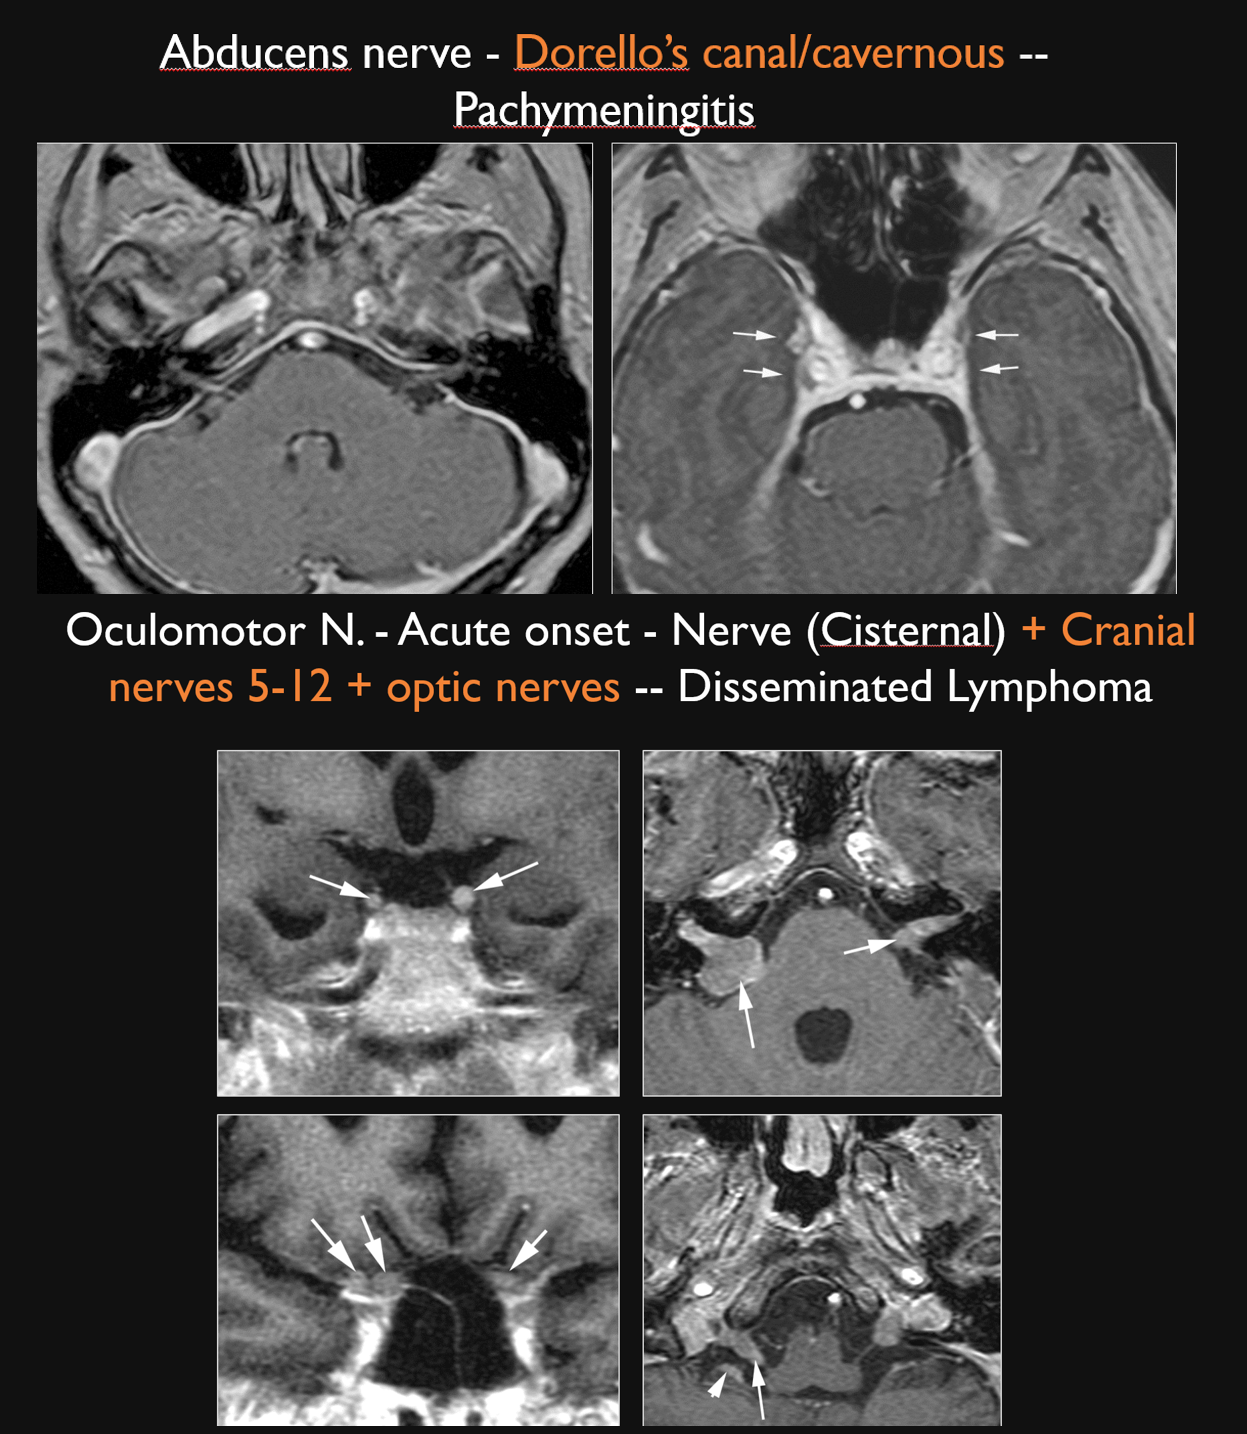

There is abnormal meningeal enhancement along the cisternal segment of the third, fourth and/or sixth cranial nerve or the point of entry of these nerves into the cavernous sinus and paracavernous dural envelope. [Yes/No]

There is an infiltrating process or structural abnormality in the region of Dorello’s canal. [Yes/No]

There is abnormal enhancement and/or enlargement of the 3rd, 4th or 6th cranial nerve in the cavernous sinus or paracavernous region. [Yes/No]

There is a structural abnormality along course of the third, fourth and/or sixth cranial nerve within (sixth) and/or adjacent to (third and fourth) the cavernous sinus. [Yes/No]